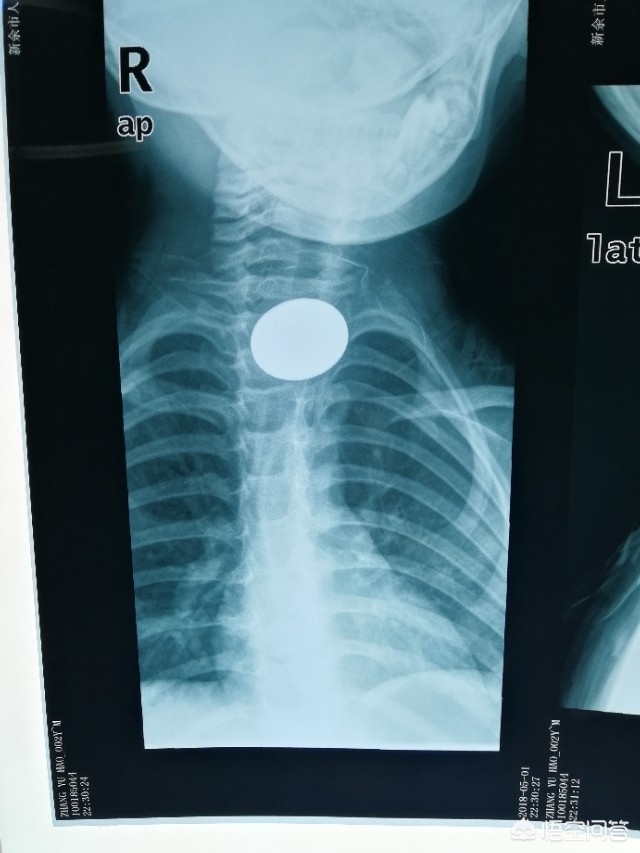

回到问题,这个血的教训一定要警醒其他的家长朋友。对待儿童一定要足够小心,我们临床经常碰到儿童气道异物,食道异物,各类本可避免的锐利物外伤。